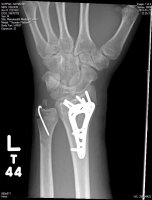

Good to hear you are doing okay and spirits are up.not real bad! bout a 5.

i didnt have time but i tried. mind you i was stuck in the bike anyhow so"i endoed my bike 6-8 feet up at ram jam, put my arms out and got landed on by my bike"

Am I the only one that will say it?.................."Tuck and Roll, Tuck and Roll" "NEVER PUT YOUR ARMS OUT!"

OK, I said it. Sorry for the mishap YD. Speedy recovery to you. One more thing..............................

TUCK AND ROLL!!!!!![]()